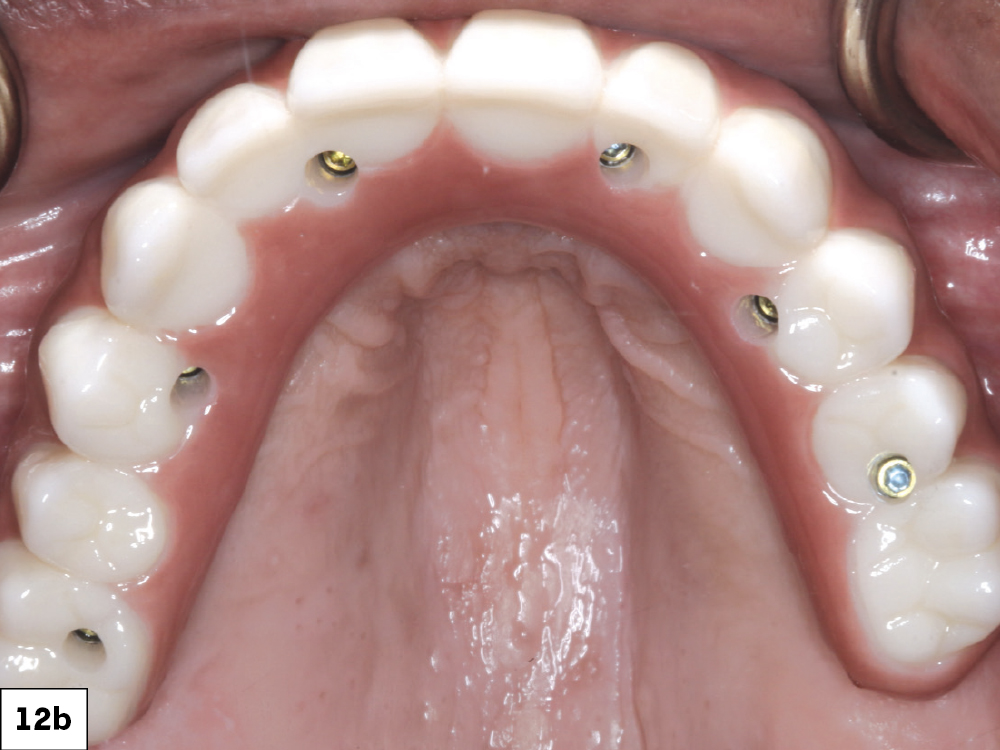

Figures 12a–12c: Once the first denture setups were tried in over the multi-unit abutments and approved, a polymethyl methacrylate (PMMA) provisional was milled. I then inserted this prosthesis and verified esthetics and function.